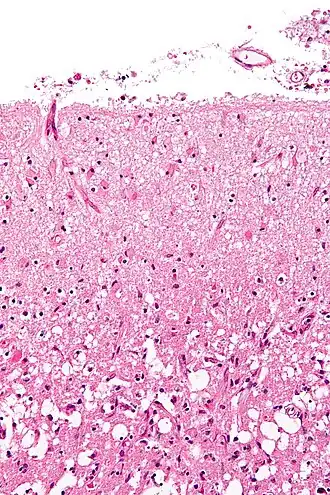

An autopsy of stroke may be able to establish the time taken from the onset of cerebral infarction to the time of death.

Various microscopic findings are present at times from infarction as follows:[32]

-

Micrograph showing cortical pseudolaminar necrosis, a finding seen in strokes on medical imaging and at autopsy. H&E-LFB stain. -

Micrograph of the superficial cerebral cortex showing neuron loss and reactive astrocytes in a person that has had a stroke. H&E-LFB stain.